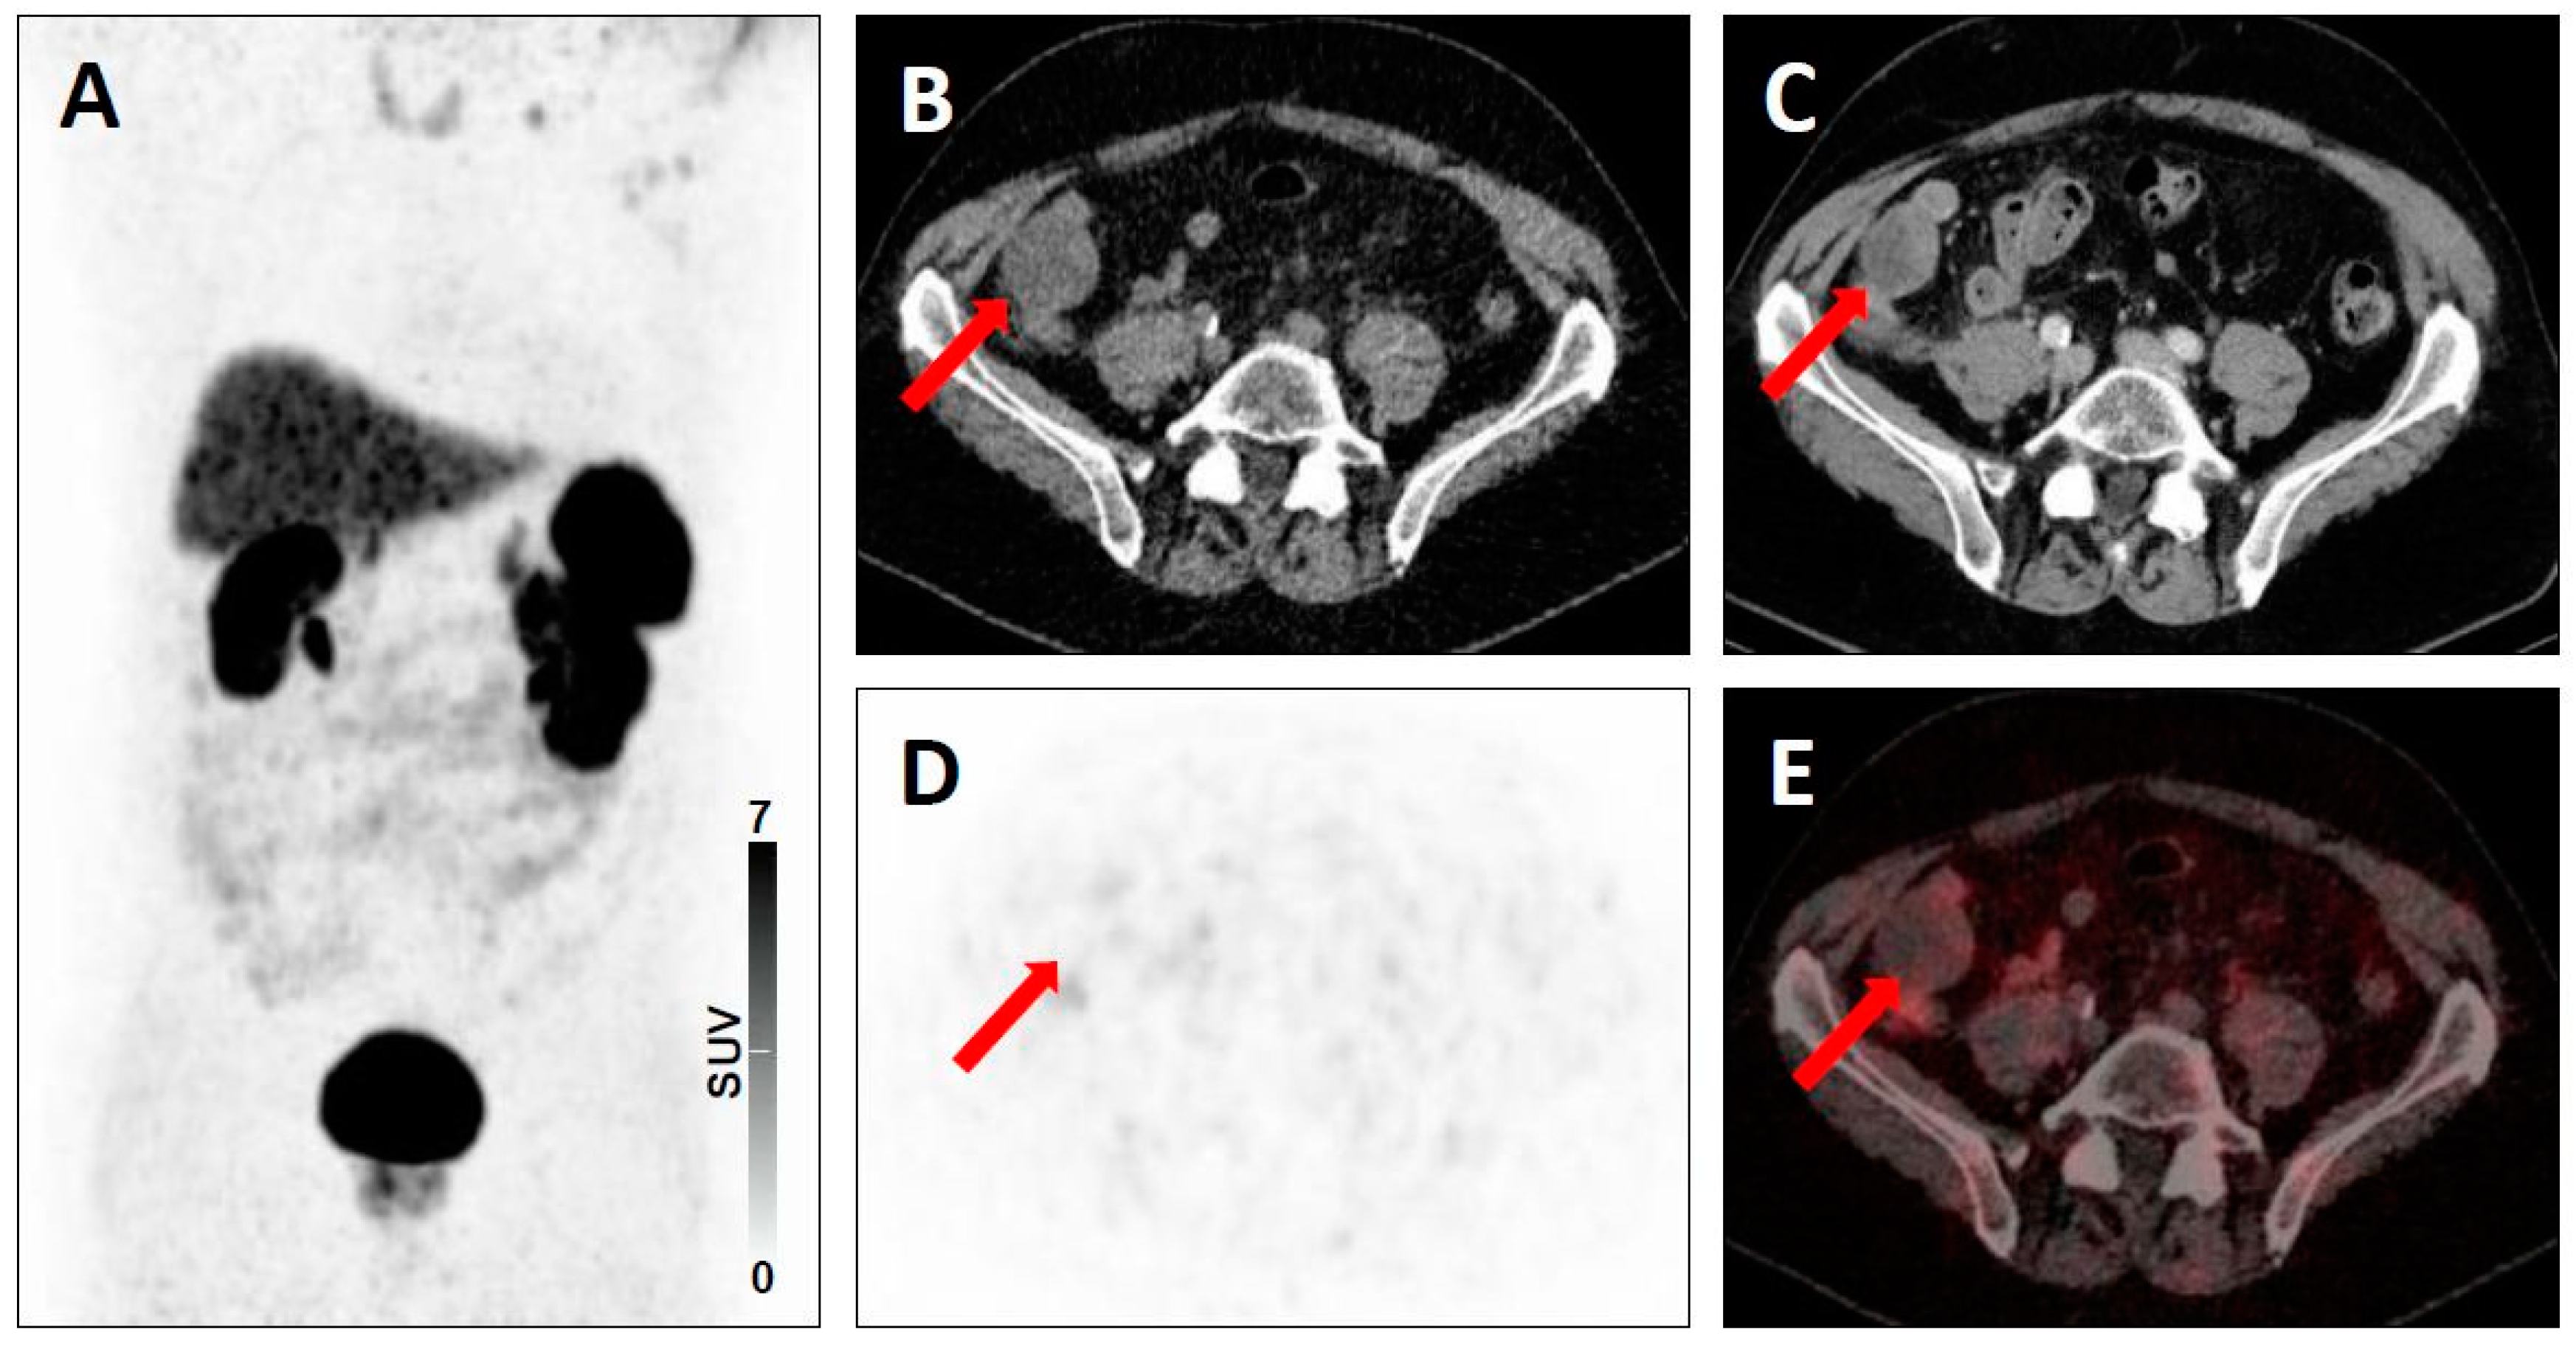

| 3B | - Low-level uptake in a rib with lack of anatomic correlate [20] | - Low level-uptake in the iliac bone with lack of anatomic correlate [19] | |

| 4 | - Intense uptake in a liver lesion without definitive findings on conventional imaging [20] | - Intense radiotracer uptake in a lymph node without definitive findings on conventional imaging [19] | |